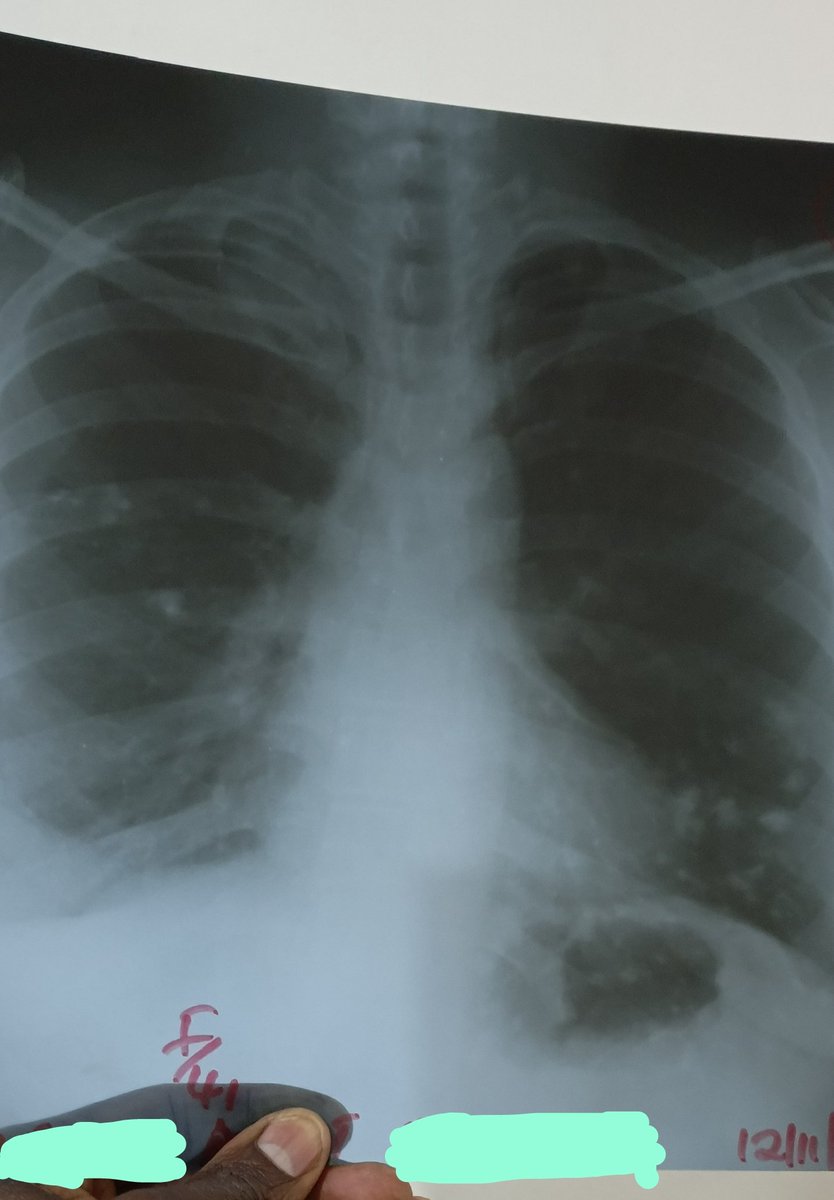

CXR. ➡️Interpret XR findings. ➡️What is the likely diagnosis? Thank you.